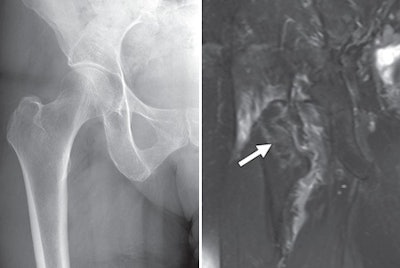

| Images are of an 80-year-old female patient with osteopenia and radiographically occult intertrochanteric fracture of the right hip. The anteroposterior x-ray image (left) does not show a fracture, while the coronal fat-suppressed T2-weighted MR image (right) shows marrow edema consistent with nondisplaced fracture (arrow). Images courtesy of the American Journal of Roentgenology. |

Most important, MRI discovered 23 fractures of the hip or pelvis among 13 patients (14%) with normal x-ray findings. In another 15 patients who had abnormal x-ray findings, MRI detected 12 additional pelvic fractures not identified on the x-rays.